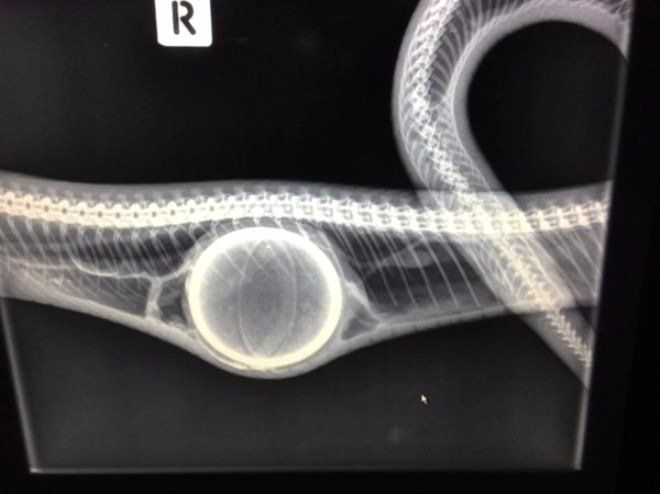

Hayvanat bahçesindeki bu kaplumbağa, son zamanlarda yürümekte zorluk çekince veterinerlerin operasyonu sonucu kurtarıldı.